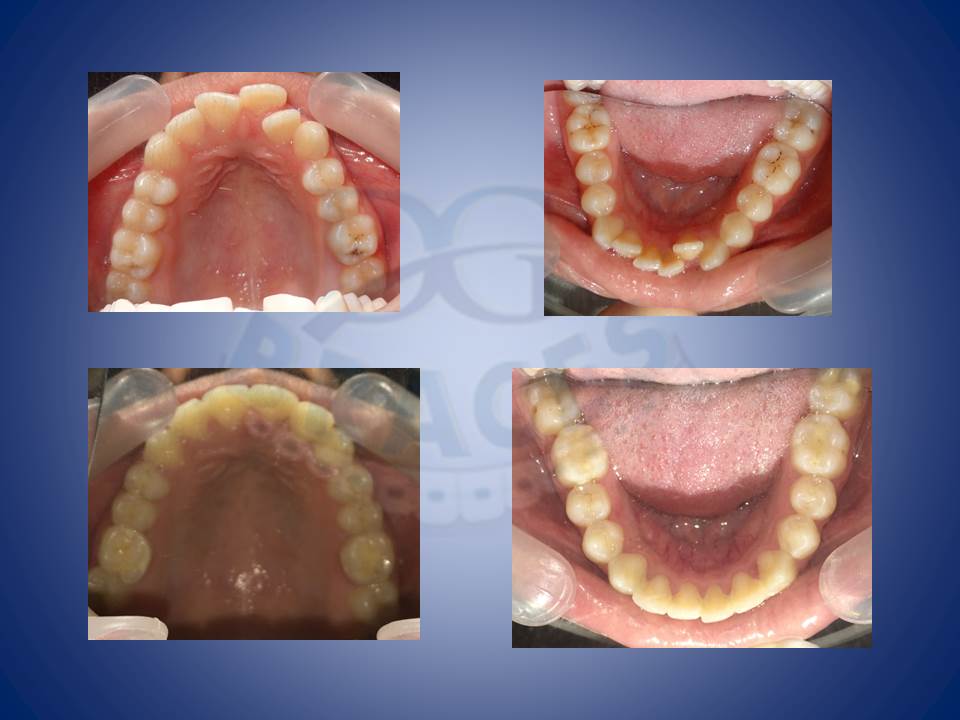

1.Crooked teeth are most often something which patients feel the need to be corrected. This is how we do it!!!

2.Crowding and multiple mutilated teeth are best left treated helping maintainance easy and improving the biting efficiency of patients upto 80%